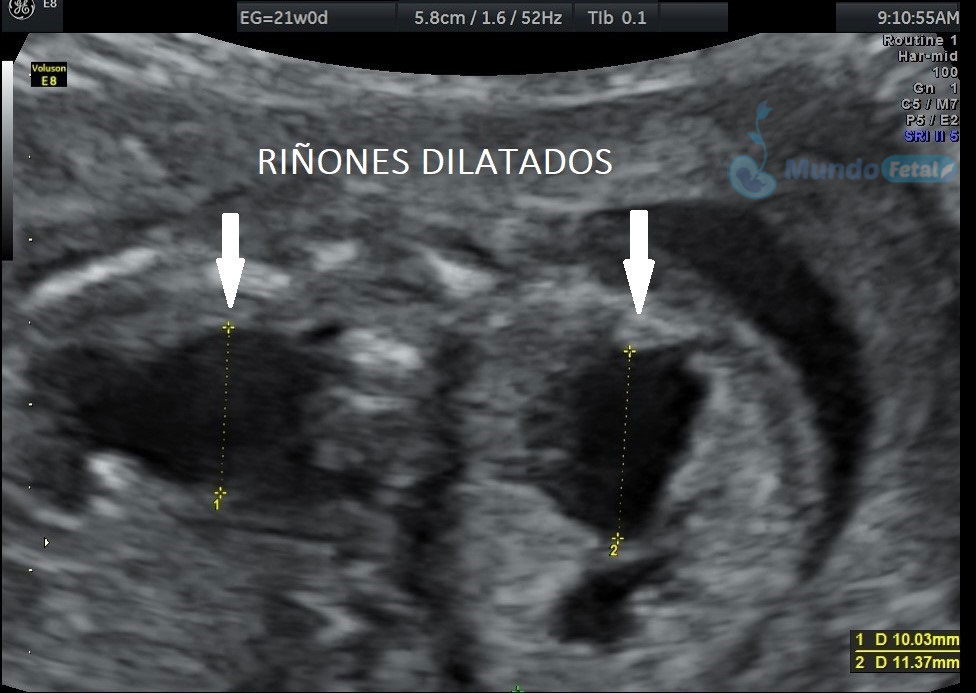

Estudio llevado a cabo en todo bebe, en quien se haya detectado alguna alteración anatómica o marcador de riesgo, valorando todos sus órganos, aparatos y sistemas, de manera específica y detallada.